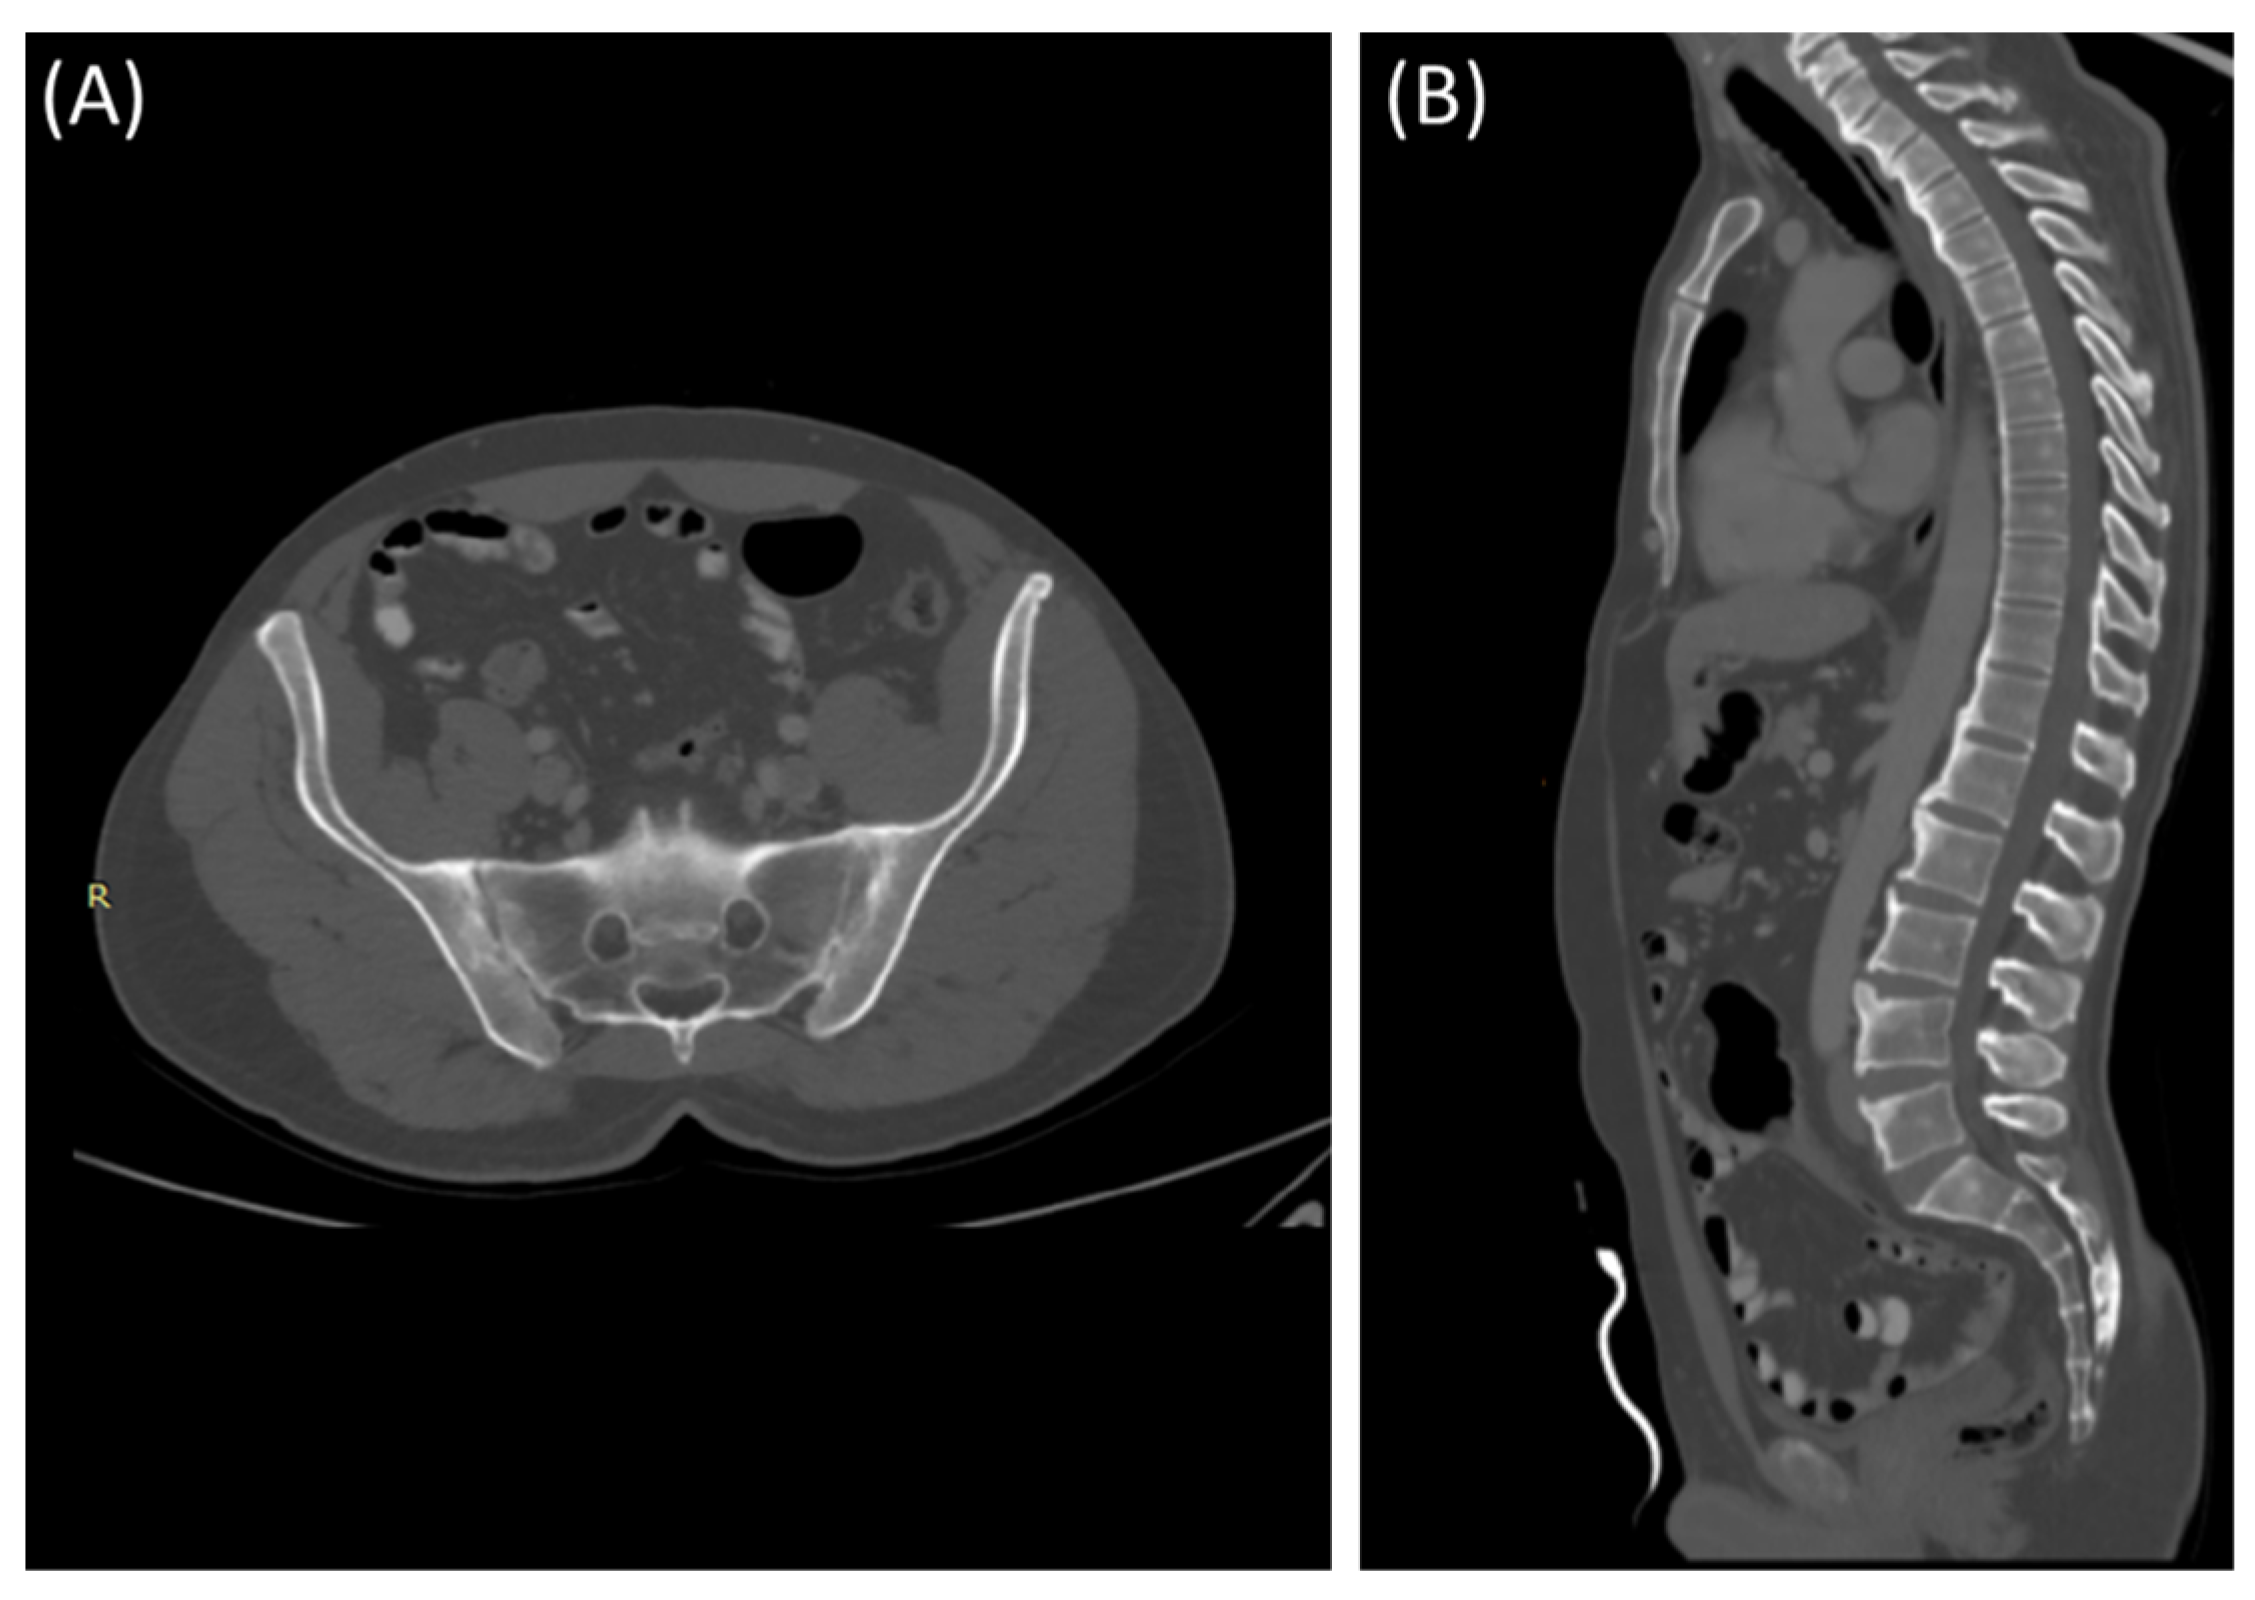

MRI is considered the gold standard for the diagnosis of sacroiliitis, especially in early and inflammatory stages [5]. It provides valuable information for diagnosing and monitoring the condition, assessing disease activity, and guiding treatment decisions [5].

As demonstrated in Figure 4, MRI is particularly sensitive in detecting active inflammation [44]. In sacroiliitis, MRI often reveals edema (swelling) and increased signal intensity on T2-weighted images within and around the SIJ [13]. This edema is indicative of active inflammation and is a hallmark feature [13].

MRI can reveal soft tissue changes, including inflammation of the ligaments and tendons around the SIJ [50]. Enthesitis, which is the inflammation of the insertion points of ligaments and tendons into bone, is a common finding in sacroiliitis and can be visualized [53]. Furthermore, a contrast agent (gadolinium) may be used to enhance areas of active inflammation, making them more visible [54]. In advanced cases, particularly in ankylosing spondylitis (Figure 6), MRI may show evidence of joint ankylosis, where the sacroiliac joint becomes fused [44].

Figure 6.

Coronal T1-WI image (A), coronal T2-WI image (B) and coronal T2-fat suppression image (C) showing sclerosis and mild irregularity in both sacroiliac joints, more on the left side with no evident bone marrow edema in a 52-year-old female with chronic low back and hip pain suggestive of bilateral chronic sacroiliitis.

As shown in Figure 7, fat suppression techniques or fat saturation sequences are often used in MRI to suppress the signal from fat tissue, making it easier to identify areas of inflammation and edema [55,56].